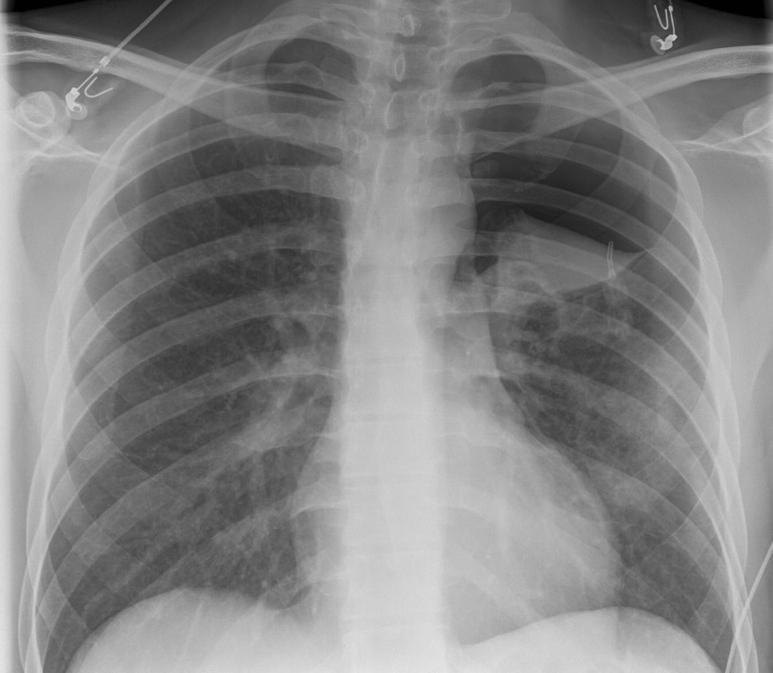

Tension Pneumothorax